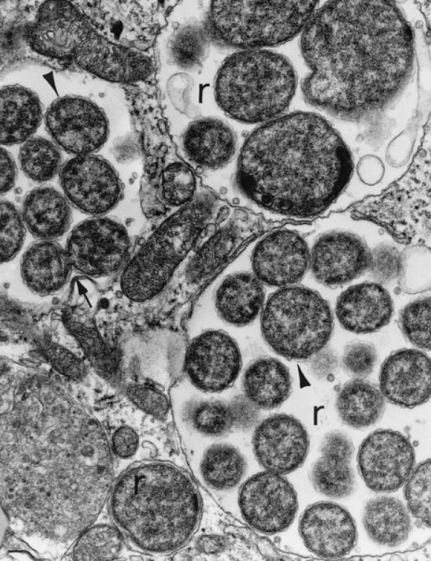

查菲埃立克体为严格细胞内寄生菌,常用的培养细胞有犬组织细胞瘤系DH82细胞、人肺成纤维细胞(HEL)、鼠胚胎细胞等。查菲埃立克体在DH82细胞中培养,可见细胞边缘具有突出的褶皱外细胞膜(图1)。在人抗凝全血中,可以存活11天。4-6℃条件下,在细胞培养基中可存活21天[1]。

图1 查菲埃立克体在DH82细胞中培养特征[1]